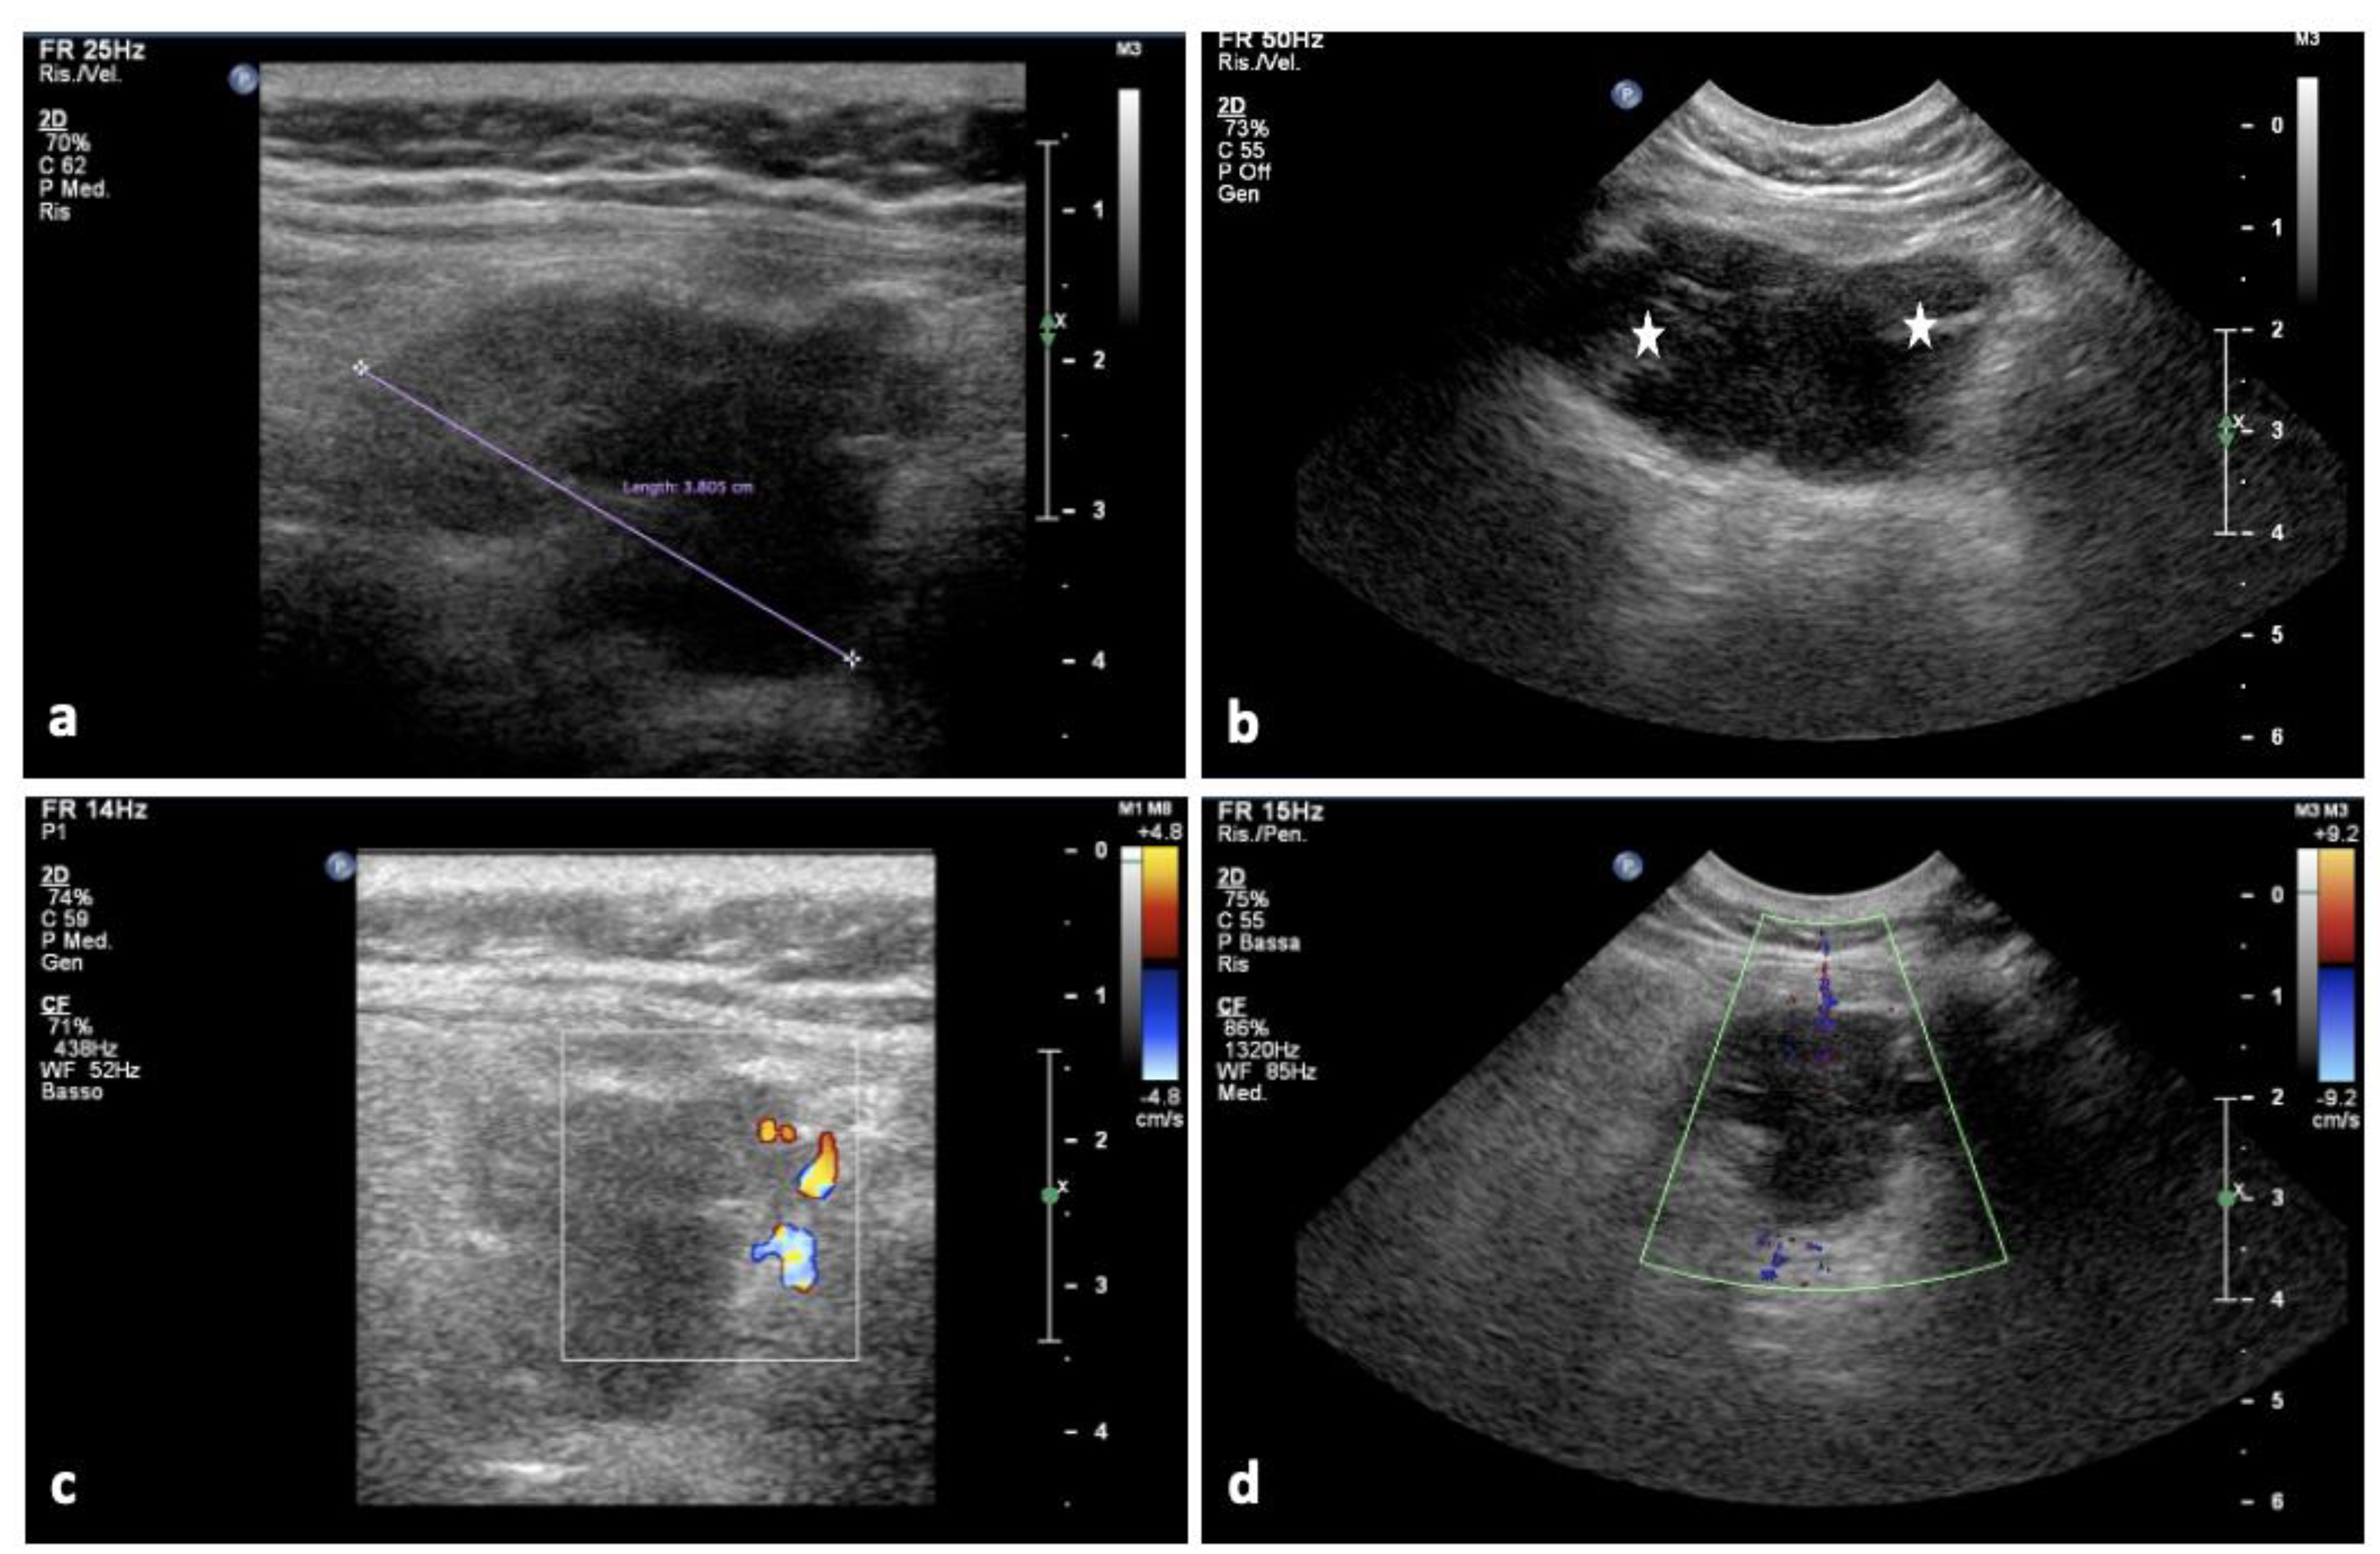

| U/S | Hypo-anechoic formation with poly lobate margins | Hyperechoic relative to the adjacent muscle | Heterogenous, multi-lobulated, typically well-defined mass of variable ultrasonographic appearance | Non-specific; hypoechoic | Well-defined hypoechoic mass; hyperechoic rim (the bright rim sign) |